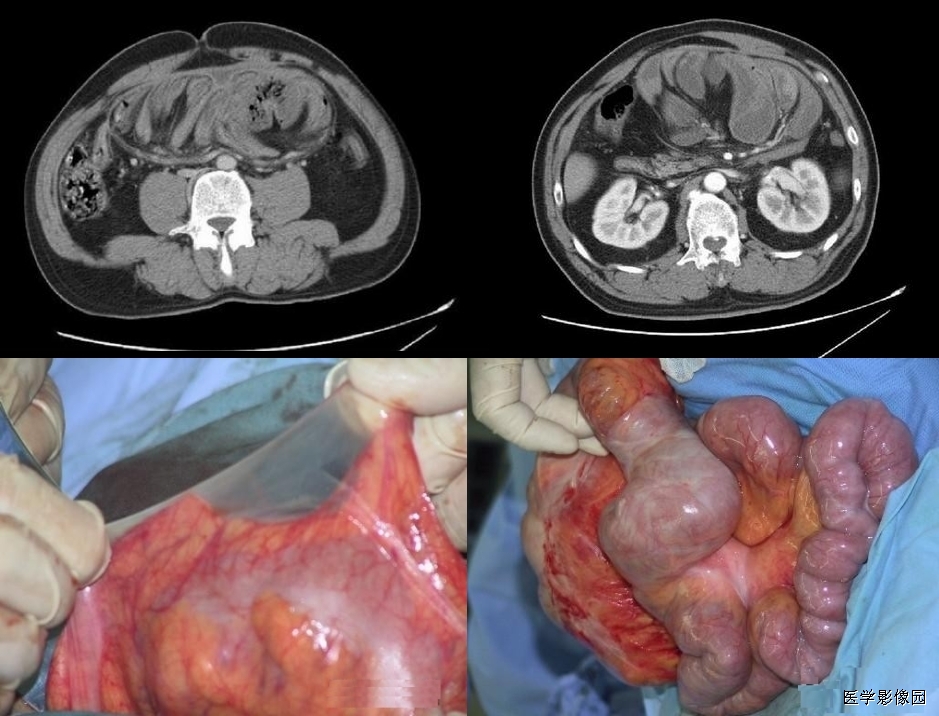

5、肠系膜混浊征

上两幅图:肠系膜上动脉栓塞

下两幅图:十二指肠扭转致肠壁增厚、肠系膜水肿